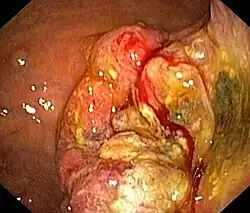

Die gebräuchlichste Methode zur Diagnose eines Magenkarzinoms ist die Magenspiegelung. Im Rahmen dieser Untersuchung sind Gewebeproben zu entnehmen, da nur eine histologische Untersuchung Art und Dignität des Tumors sicher feststellen kann. Um diese Methode zu verbessern, wurden mehrere Farbstoffe entwickelt, die auf die Magenschleimhaut aufgetragen werden können. Der Farbstoff Methylenblau wird von Oberflächenzellen des Darmes aufgenommen. Der Nachweis von Darmschleimhaut im Magen oder der Speiseröhre ist ein Hinweis auf einen bösartigen Prozess oder eine Vorstufe dessen. Die Farbstoffe Indigokarmin und Kresylviolett verstärken den Kontrast des Schleimhautreliefs und lassen so Unregelmäßigkeiten leichter erkennen. Des Weiteren ist mittlerweile die Zoomendoskopie verfügbar, bei der die Schleimhaut unter 15- bis 150-facher Vergrößerung beurteilt werden kann. Eine weitere Technik ist das Narrow-Band-Imaging. Dabei wird durch einen Filter der Blauanteil des Lichts erhöht, so dass auch Unregelmäßigkeiten in der Schleimhaut besser gesehen werden können.[11]

Man unterscheidet je nach der Form des Tumorwachstums vier Typen von Adenokarzinomen des Magens. Das polypoide Adenokarzinom wächst wie ein Polyp von der Mageninnenseite in das Magenlumen ein. Das ulzerierende Adenokarzinom zeichnet sich durch die Bildung einer Schleimhautschädigung im Sinne eines Geschwürs aus. Gegenüber gutartigen Magengeschwüren zeigt das Karzinom unregelmäßigere Ränder. Beide Typen machen je ein Drittel der Magenkarzinome aus. Rund ein Zehntel aller Magenkarzinome sind vom diffusen Typ. Diese Tumoren wachsen nicht in das Lumen ein, sondern infiltrieren das Gewebe des Magens. Die Tumorzellen induzieren eine Fibrose in der Schleimhaut- und der Muskelschicht des Magens, was zu einer Wandverdickung führt. Der diffuse Typ ist mit einer besonders schlechten Prognose assoziiert. Als Frühkarzinom des Magens bezeichnet man einen Tumor, der auf die Schleimhaut oder die Submukosa beschränkt bleibt. Obwohl rund 20 % der Frühkarzinome bei Diagnosestellung bereits metastasiert haben, besitzen sie im Vergleich zu den anderen Arten eine relativ gute Prognose.[13]